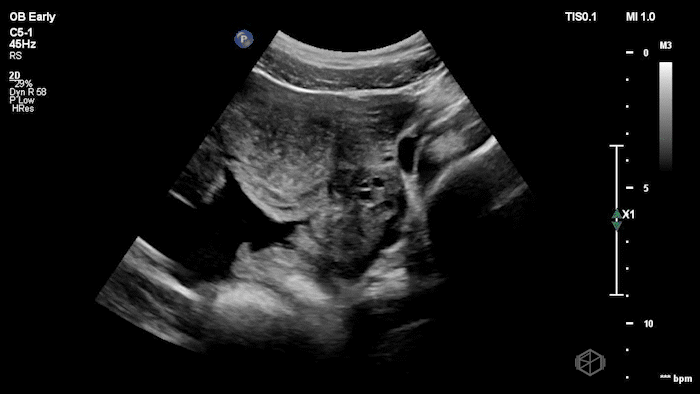

04 - What is the most likely diagnosis and definitive next step for this patient?

Left adnexal complex mass with significant free fluid concerning for ruptured ectopic pregnancy (OB Early setting).